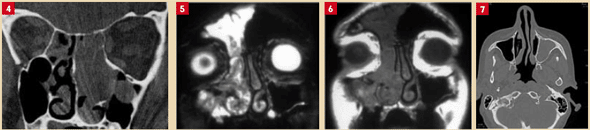

Imagerie

L’imagerie (scanner des sinus, dentascan, IRM) occupe une place de choix pour préciser le diagnostic, sans pour autant supplanter l’examen clinique et endoscopique. Les indications d’imagerie sont guidées par les données recueillies et les particularités de chaque cas. Parfois, la corticothérapie récente peut brouiller l’interprétation des images, d’où l’intérêt d’une bonne coordination entre cliniciens et radiologues.

Les protocoles modernes permettent des reconstructions multiplanaires (axiales, coronales, sagittales) et même des vues panoramiques pour des situations dentaires particulières. En cas de suspicion tumorale, l’IRM avec injection de gadolinium précise les relations avec les structures voisines et distingue tumeurs et inflammations.

Le scanner offre une cartographie fine des sinus et de leurs rapports avec les structures orbitales, vasculaires ou nerveuses. Les reconstructions 3D aident à visualiser les variations anatomiques et à anticiper les risques chirurgicaux.

L’examen évalue la perméabilité nasale, la position de la cloison, l’hypertrophie des cornets, la présence de concha bullosa, de synéchies ou d’anomalies osseuses. Les zones de drainage, comme le complexe ostioméatal, sont passées au crible, car leur obstruction favorise l’infection.

Dans certains cas, seul un examen anatomopathologique tranche, comme pour le diagnostic de papillome inversé : une tumeur bénigne, à croissance lente mais à potentiel malin. L’endoscopie repère une lésion évocatrice, l’imagerie précise son extension, et le traitement repose sur une exérèse large. La surveillance est impérative en raison des récidives fréquentes.

Une opacité complète du sinus maxillaire associée en endoscopie à une masse translucide dans le méat moyen peut faire suspecter un polype antrochoanal, tumeur bénigne à traiter par voie endoscopique. La mucocèle, pseudokyste sécrétoire, progresse lentement, provoque des déformations et se repère à l’imagerie par son aspect expansif. Là encore, la chirurgie s’impose.

La figure illustre un cas d’obstruction nasale unilatérale persistante, liée à un gonflement muriforme visible en endoscopie, révélant un papillome inversé. L’IRM met en évidence l’aspect spécifique de la lésion. Un polype antrochoanal, quant à lui, se manifeste par une obstruction nasale chronique et une rhinorrhée persistante, nécessitant une exérèse complète pour éviter les récidives.